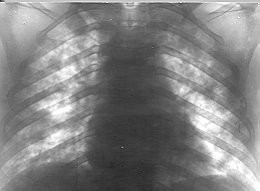

characterized by the appearance of focal infiltrative shadows. A typical observation in

the majority of cases was the localization of the changes on the periphery of the

pulmonary fields as well as in the gravitation-dependent segments (60%) (Figs. 1-3). The

| Fig. 1 -

Alveolar pulmonary oedema. |

Fig. 2 - Respiratory

distress syndrome. |